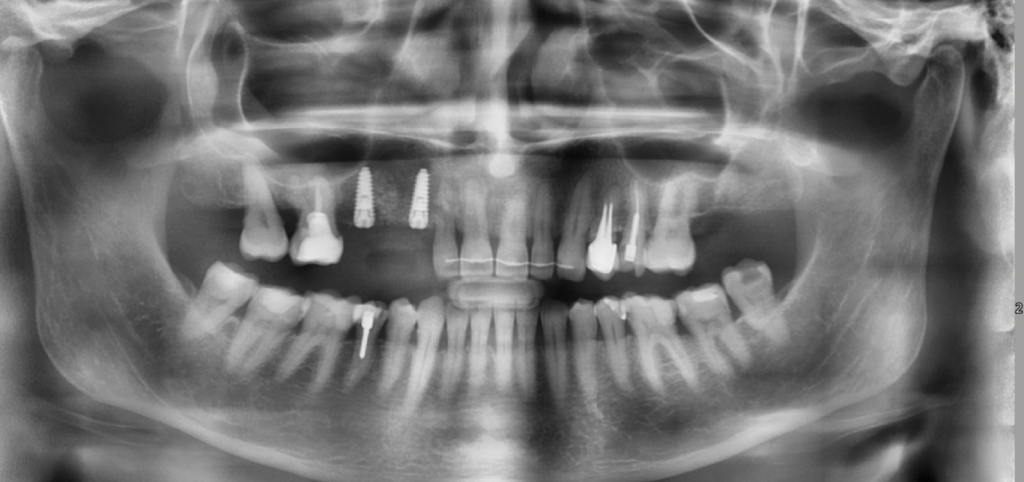

Описание клинического случая:

• Атравматичное удаление зуба 2.4, 2.5

• Одномоментная дентальная имплантация IMPRO

• Использование фибриновой мембраны Clot-PRF

• Установка временного абатмента IMPRO

• Изготовление индивидуального формирователя десны

Клинический случай Узденовой Зульфы Альбертовны